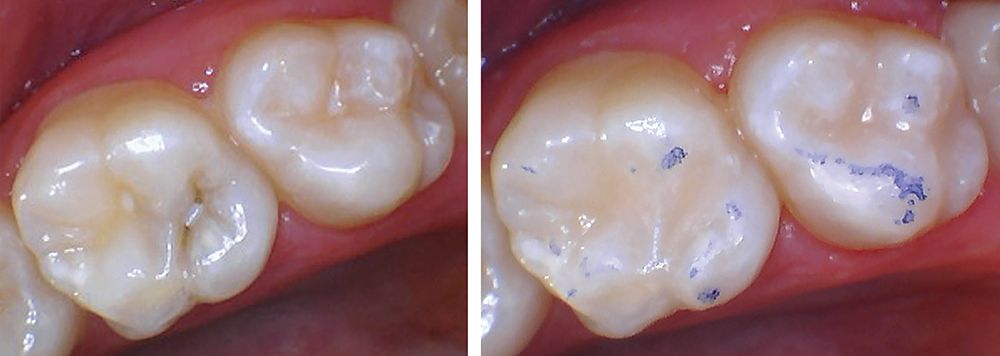

Clinical image courtesy of Shukan Kanuga DDS, MSD.

Clinicians can use Beautifil Kids SA for preventive resin restorations, small Class I, and other non–load-bearing restorations without the need for a bonding agent. The flowable composite’s unique chemistry provides a chemical bond and resin tag infiltration.

Ideal for the management of caries in restless children, it features Shofu’s exclusive Giomer Technology that releases and recharges fluoride and other beneficial ions for the life of the restoration. As a result, patients receive healthful benefits such as antibacterial effect, acid neutralization, tooth structure strengthening, and more.

It delivers high bond strength for reliable adhesion, precision placement with superior handling, and light transmission and diffusion properties that blend well with primary or permanent dentition for picture-perfect restorations. The lack of a bonding agent allows total integration of the healthful benefits, including antibacterial effect, acid neutralization, fluoride release and recharge, and more.